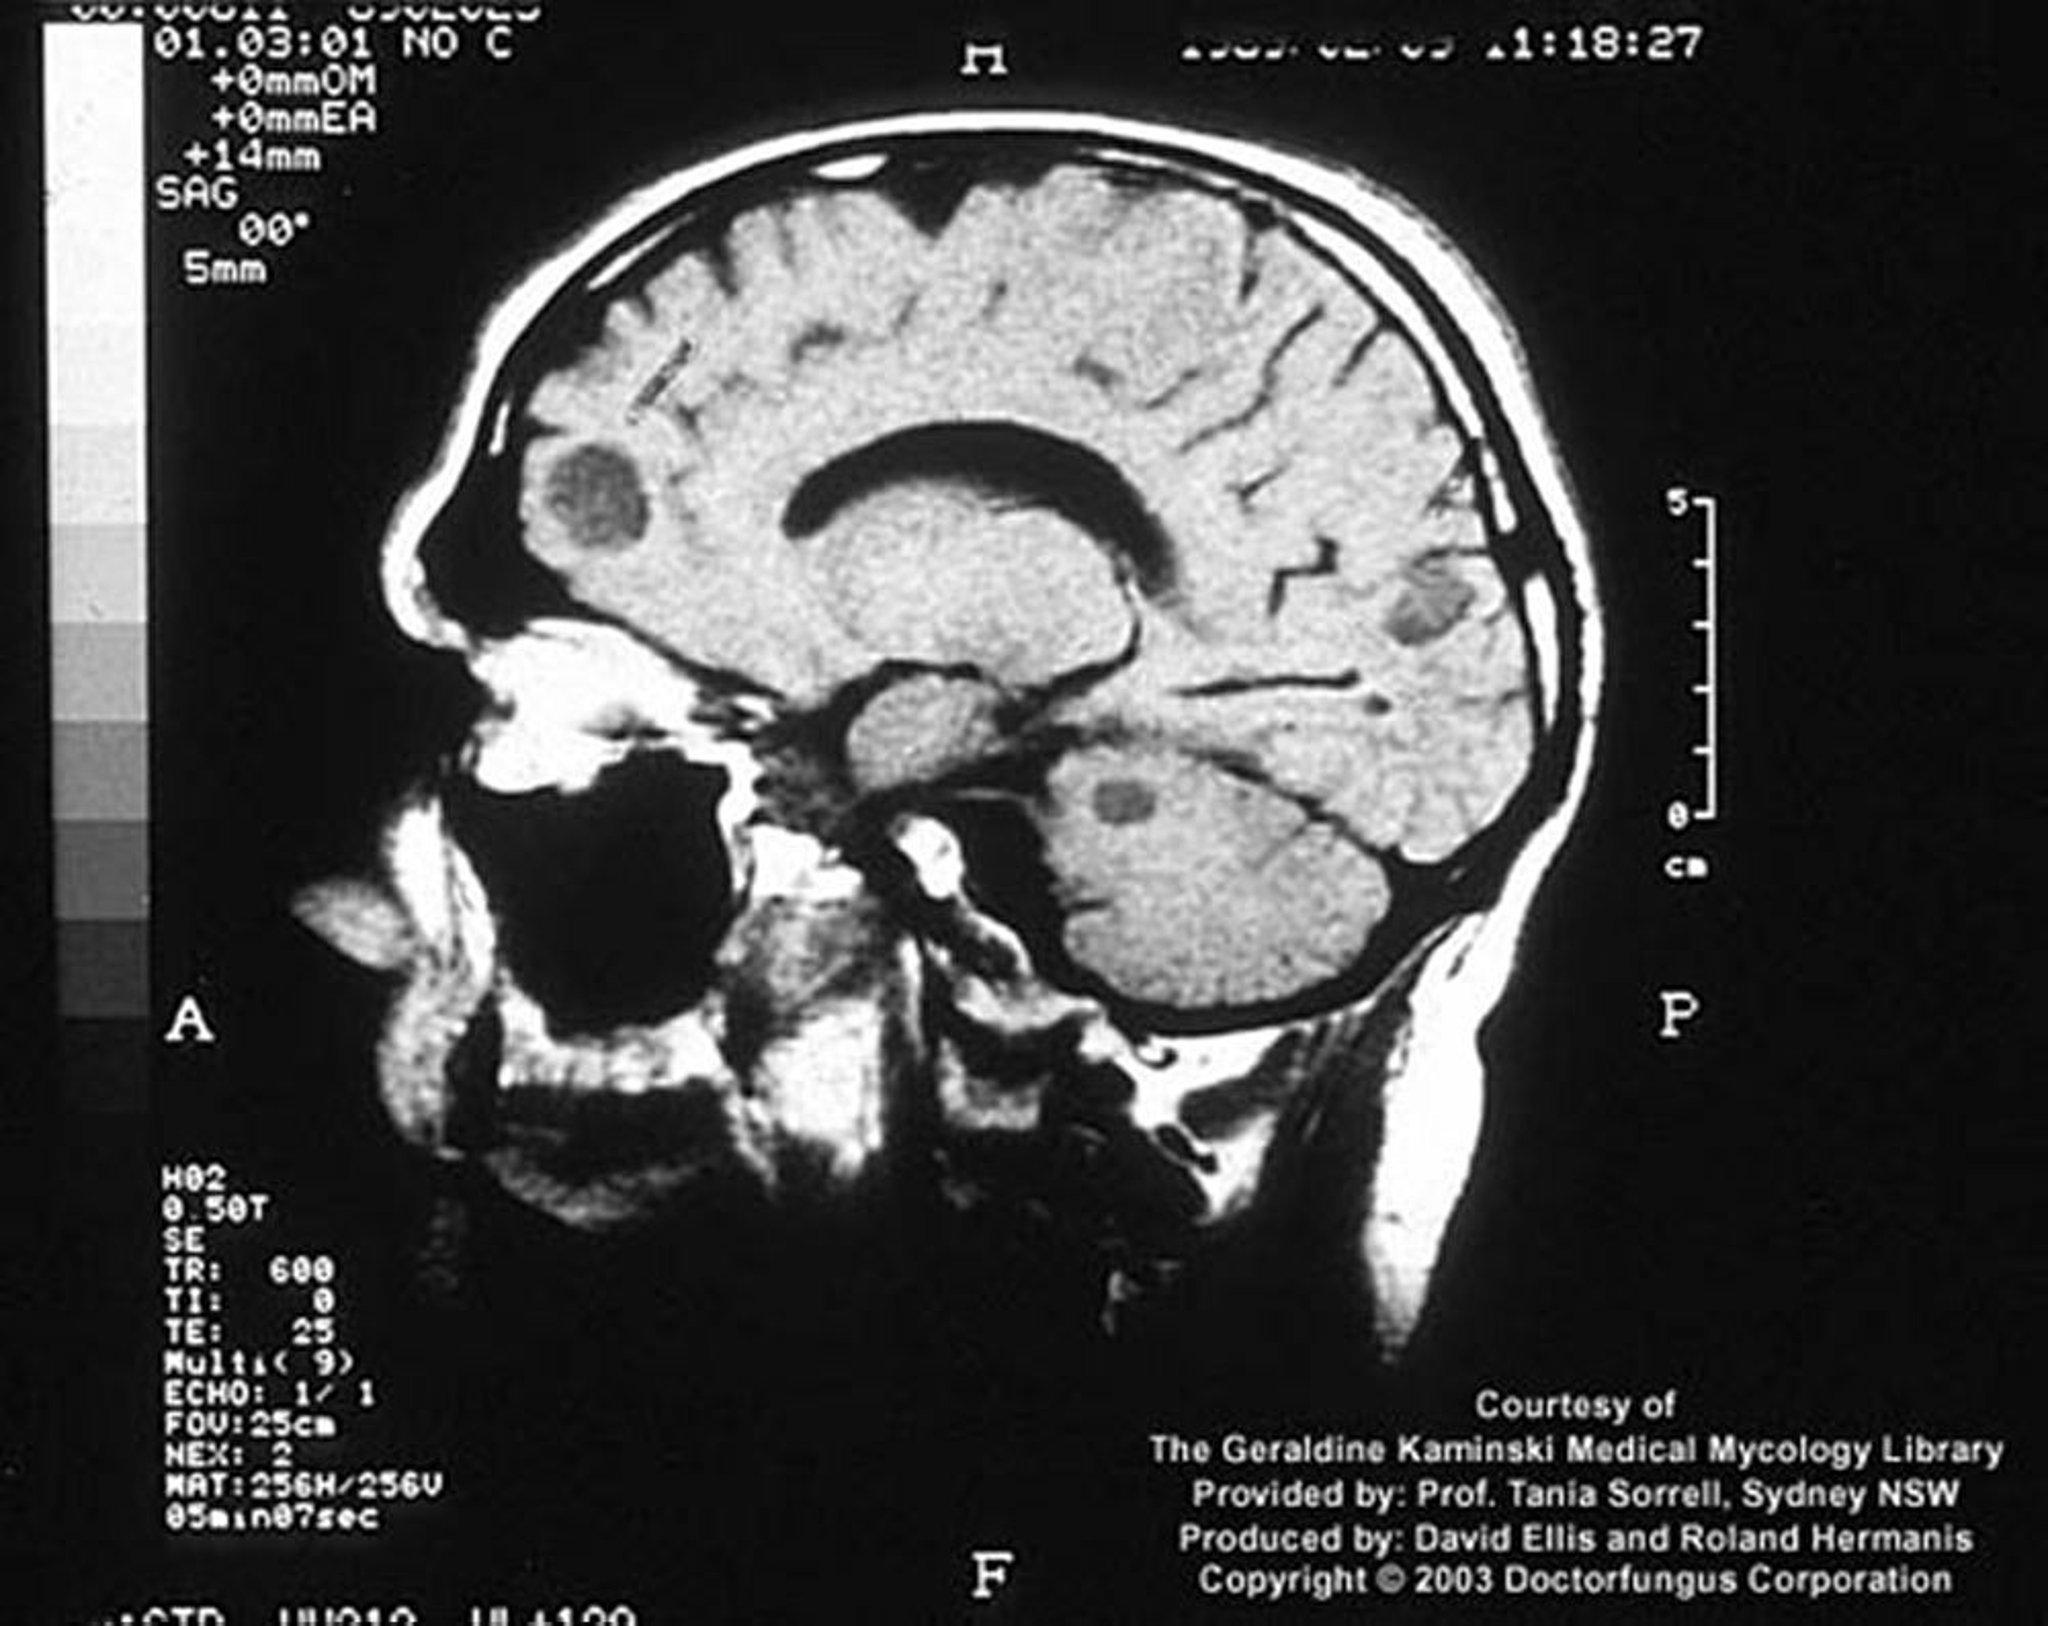

Kryptokokkose (Zentralnervensystem)

Bei einem immunsupprimierten Wirt kann sich eine Kryptokokkeninfektion als fokale Hirnläsionen, sog. Kryptokokken, manifestieren.

Image courtesy of www.doctorfungus.org © 2005.